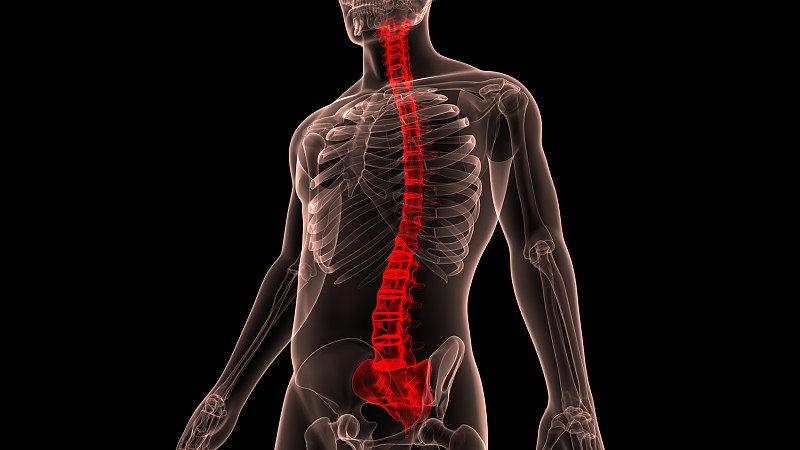

男性背部疼痛解剖黑色详情

男性背部疼痛解剖黑色详情

男性背部疼痛解剖黑色详情